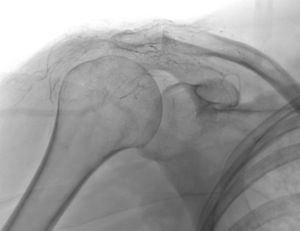

L’embolisation de la capsulite rétractile est une innovation récente qui cible la cause profonde de l’inflammation : l’hypervascularisation. Dans une épaule gelée, de petites artères anormales se développent autour de la capsule, alimentant le processus inflammatoire et la douleur.

Grâce à l’imagerie de précision (angiographie), le radiologue interventionnel identifie ces vaisseaux « anormaux » et les occlut sélectivement. En bloquant leur flux sanguin, on réduit l’apport en oxygène et nutriments à la zone enflammée, favorisant une résolution rapide des symptômes.

- Accès vasculaire : mise en place sans incision d’un cathéter fin dans l’artère radiale du côté de la capsulite.

- Guidage par imagerie : Le cathéter est avancé jusqu’à l’artère sous-clavière sous contrôle radioscopique en temps réel.